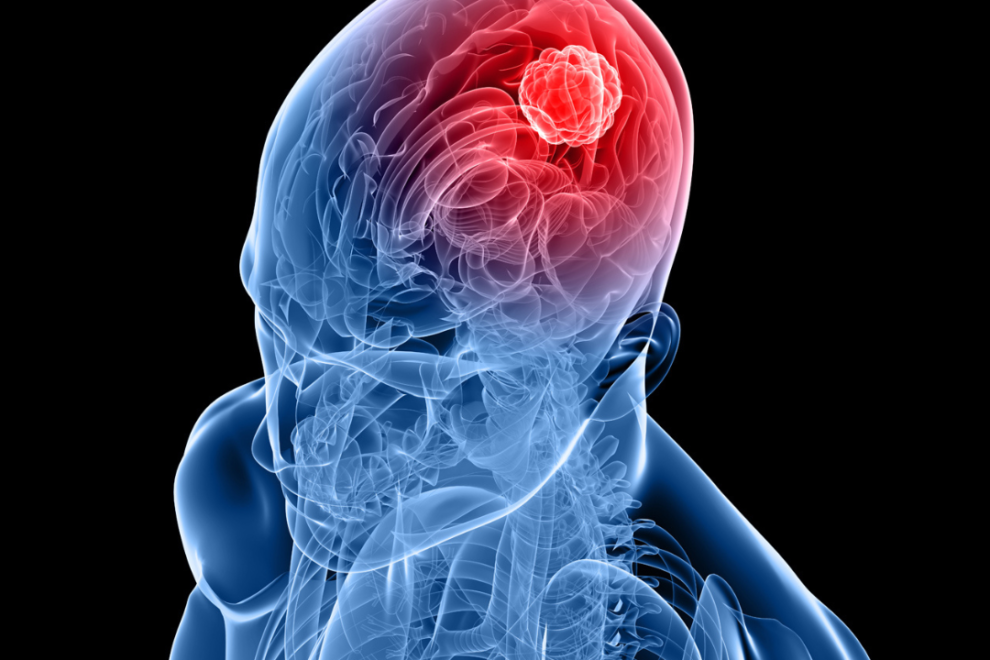

Metastatic Tumors Treatment and cost in India

Metastatic disease can be viewed as two simultaneously occurring diseases. Brain cancer and systemic cancer (elsewhere in the body). Each disease has quite different mortality rates. Untreated brain metastases are rapidly fatal, while systemic cancer may not be. Metastatic brain disease is a focal disease and focal control of the tumor is paramount to patient survival. The approach in the past has been to treat metastatic brain disease as a whole brain disease, with whole brain radiation (WBR). Because of poor local control of tumor growth when treated solely by WBR, brain metastases in the past were rapidly lethal. Therefore patients with brain metastases did not benefit from many advances in cancer therapy (immuno therapy, chemo therapy, conformal radiotherapy etc.) because these therapies do no effectively reach brain metastases and individuals died quickly from neurological progression.

Symptoms of Metastatic Brain Tumors Headache in India

Headache is caused by stretching of sensitive structures such as blood vessels or nerves due to edema, spinal fluid obstruction or tumor growth, or by injury to the brain caused by the tumor. Initially, the headache comes and goes, and is usually more common in the morning, just after awakening. It gradually increases in duration and frequency.